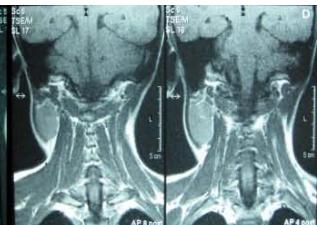

Figure/Patient 4

1. A 7 year-old girl presenting with a tumefaction at the level of the left latero-cervical region. MRI scans show a subcutaneous lesion occupying the left submandibular, parotidal, para-pharyngeal and part of the masticatory spaces. The lesion appears slightly hyper-intense on T1 (A-C) and markedly hyper-intense on T2 (D-F) scans. Diagnosis of cystic lymphangioma is done.

2. The same patient undergoing two different sessions (A-D and E-G, respectively) of sclerotherapy with absolute ethanol. An 18-G needle is introduced into the lesion and about 10 cc of citrine-turbid fluid are aspirated (B and F). Then, 5 cc of ethanol are injected and the patient is mobilised in order to distribute the SA throughout the lesion (D and G). The patient is dismissed and a one-week antibiotic therapy is prescribed.